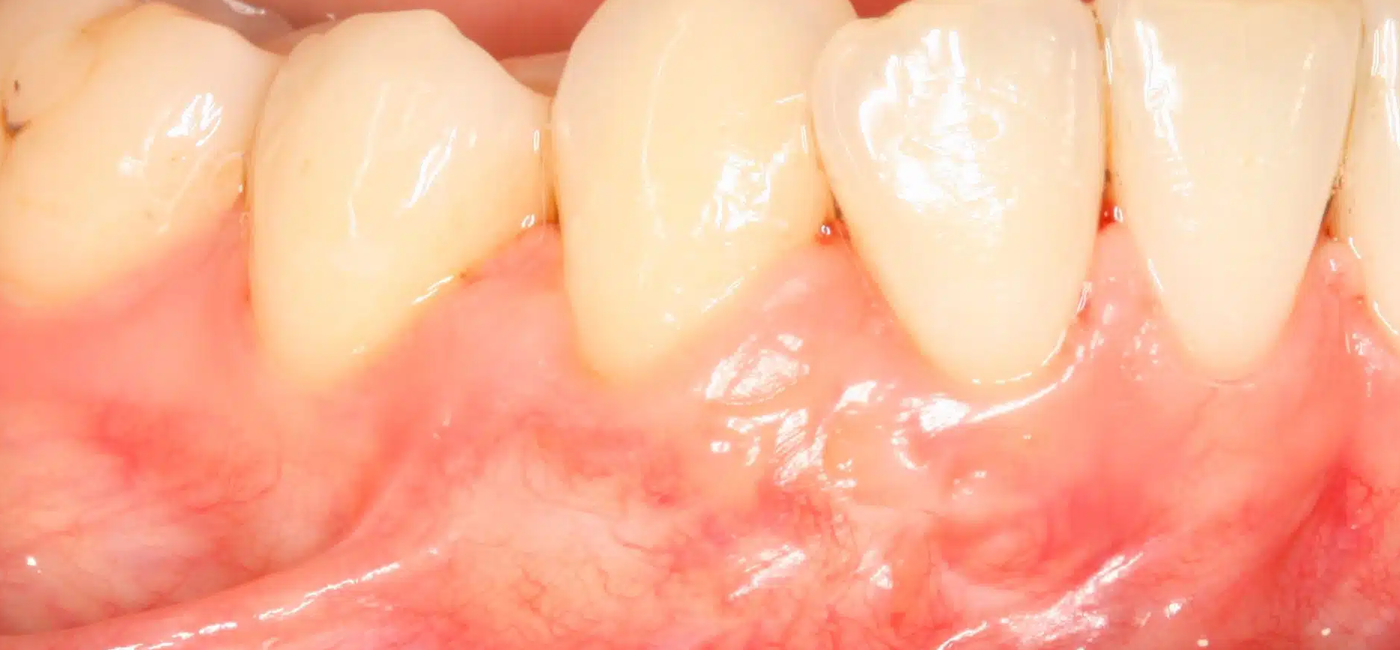

Durante el procedimiento, el odontólogo o periodoncista toma una pequeña porción de tejido, generalmente del paladar (encía del propio paciente), o utiliza materiales biocompatibles donados o sintéticos, para colocarla en la zona afectada. Este tejido se sutura y se integra progresivamente con la encía existente, cubriendo la raíz expuesta y fortaleciendo la zona. El proceso se realiza bajo anestesia local y, en la mayoría de los casos, la recuperación es rápida y poco dolorosa si se siguen las indicaciones posoperatorias.

Los beneficios del injerto de encías son notables tanto desde el punto de vista funcional como estético. Este procedimiento protege las raíces dentales expuestas, disminuye la sensibilidad al frío o al calor, detiene el avance de la recesión, facilita una mejor higiene oral y mejora la apariencia de la sonrisa al devolver una línea gingival más natural y simétrica. Además, refuerza la estabilidad de los tejidos blandos alrededor de los dientes o implantes, lo que contribuye a la salud periodontal a largo plazo.

El éxito del injerto depende de una adecuada planificación, una técnica quirúrgica precisa y una buena colaboración del paciente en el postoperatorio. Es fundamental mantener una excelente higiene oral, evitar el cepillado agresivo sobre la zona tratada y seguir las recomendaciones del especialista. En los días posteriores, se aconseja una dieta blanda, evitar fumar y asistir a las revisiones programadas.